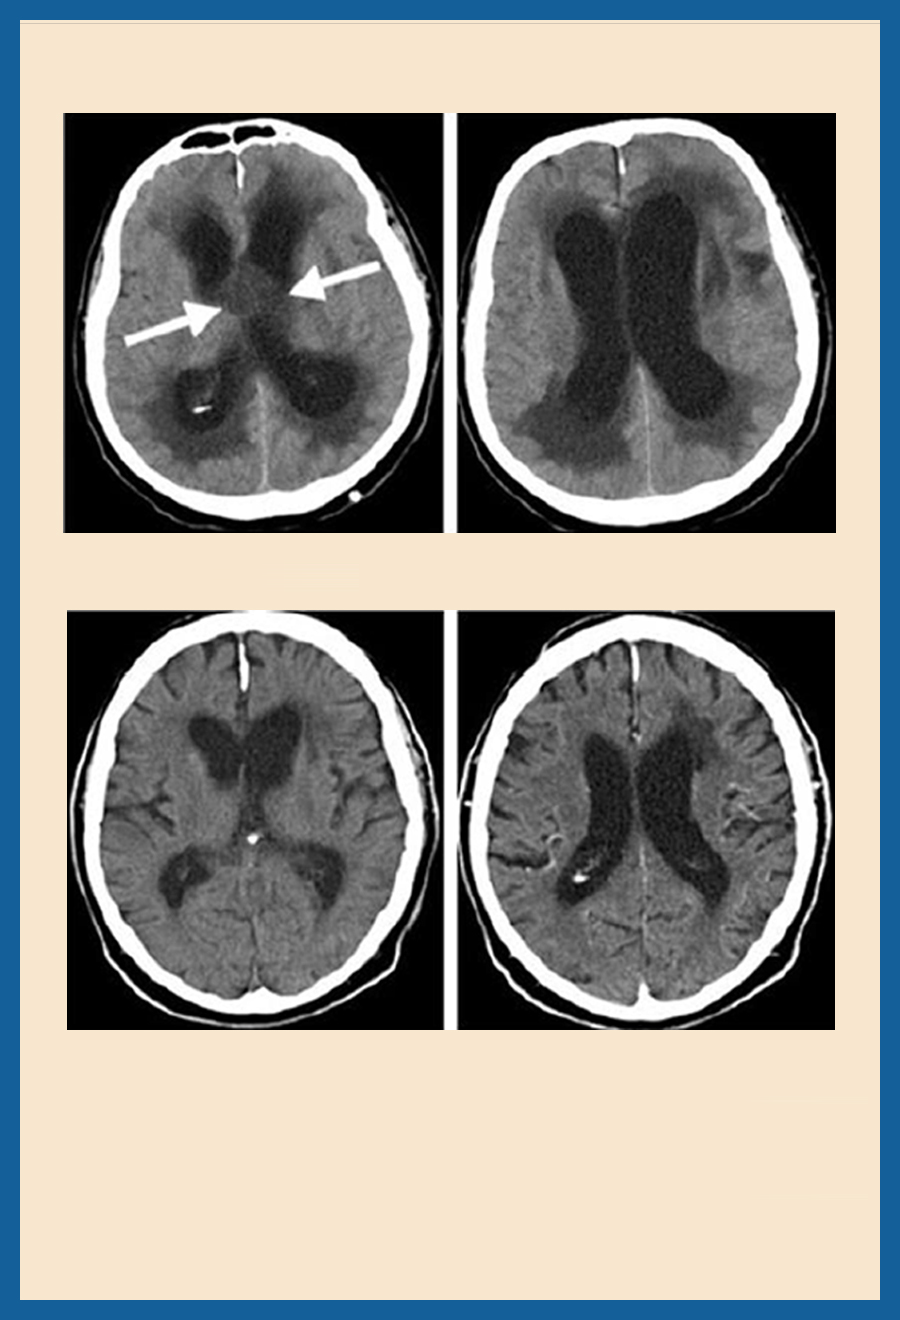

術(shù)前CT:顯示大的囊性顱咽管瘤,伴有閉塞性腦積水。三腦室中囊性腫瘤的腦室系統(tǒng)大大增大。

手術(shù)方法:小鉆孔神經(jīng)內(nèi)鏡下腫瘤微創(chuàng)切除術(shù)

術(shù)后情況:腫瘤被完全切除。腦積液循環(huán)恢復(fù)正常,術(shù)后患者恢復(fù)地很好,記憶障礙消退,垂體功能保留。